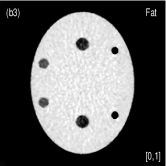

Fig. 4 shows the decomposed material images by the Direct Inversion, the PWLS-EP-LOOP and the PWLS-TNV- method. The left corners of the to the column of Fig. 4 show enlarged rods that are highlighted with white dashed boxes in decomposed material images. Table 2 summarizes the means and noise STDs of ROIs of decomposed basis material images. The volume fraction (VF) accuracies were , , and for the Direction Inversion, the PWLS-EP-LOOP and the PWLS-TNV- method, respectively. Compared with the Direct Inversion and the PWLS-EP-LOOP method, the proposed PWLS-TNV- method increases the VF accuracy by and respectively.

Table 3 summarizes the average electron densities of contrast rods and RMSE() of electron density for the three MMD methods. The RMSE() was , and for the Direct Inversion method, the PWLS-EP-LOOP method and the proposed PWLS-TNV- method, respectively. The proposed PWLS-TNV- method suppressed noise, decreases crosstalk and increased decomposition accuracy in the material images, while maintaining high image quality.